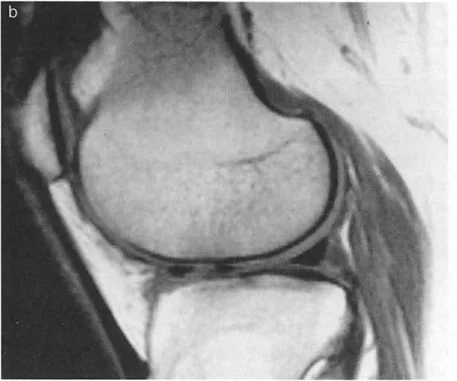

غالبًا ما يكشف التصوير بالرنين المغناطيسي عن تمزقات تنكسية أمامية في الغضروف الهلالي وآفات غضروفية متقابلة في المفصل الظنبوبي الفخذي الأمامي ناتجة عن الانحشار الأمامي المتكرر للركبة المفرطة التمدد. إذا عالج الجراح الركبة فقط (مثل استئصال الغضروف الهلالي أو قطع عظم الساق القريب)، فستفشل الجراحة لأن المحرك الأساسي للمرض - انكماش الكاحل - قد تم تجاهله.